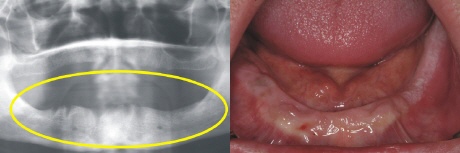

Ausgangssituation

Das Bild rechts zeigt den zahnlosen Oberkiefer. Im Röntgenbild sieht dies aus wie auf dem linken Bild (gelber Kreise).